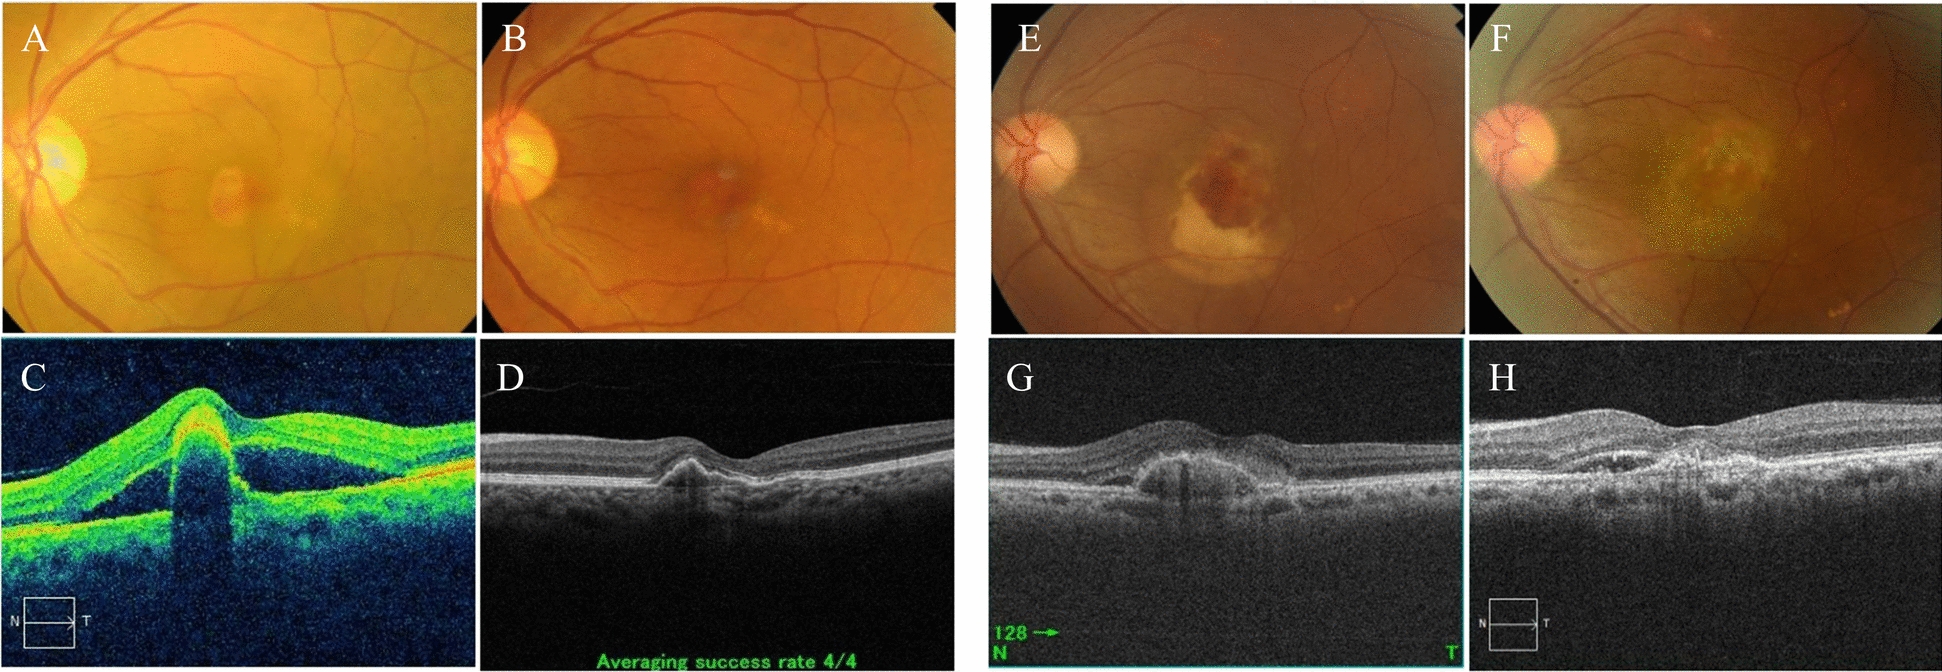

Abstract Image